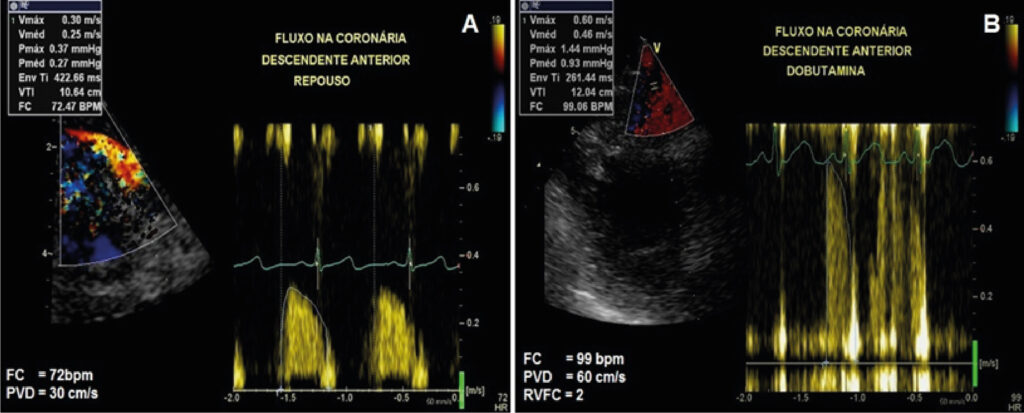

Coronary Flow Velocity Reserve and Myocardial Contractility Under Stress in the Post-Infarction Ischemic Memory Dilemma

After acute myocardial infarction (AMI), some cases progress with deep T wave inversions on electrocardiogram (ECG). This electrocardiographic abnormality can continue for a prolonged period, even if a coronary intervention within a short time of AMI progression results in successful myocardial reperfusion. However, these deep T wave inversions can raise management questions when the patient is already being followed up in an outpatient clinic, particularly in the absence of relevant symptoms to support the resurgence of an ischemic process. In this context, a safe noninvasive assessment such as dobutamine stress echocardiography (DSE) associated with the analysis of coronary flow velocity reserve (CFVR) may be an option for this dilemma between myocardial ischemia and the possible post-infarction ischemic memory. –